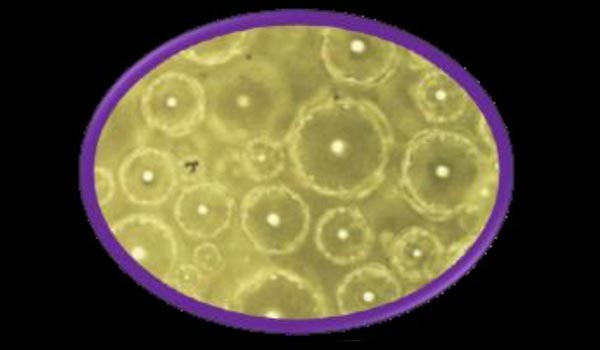

SE-Form

- • Uniformly sized and shaped microspheres

- • Particle size can be controlled to meet delivery requirements

- • Release profiles can be varied by applying ZSmartCoat or other polymers, Carbohydrates, and waxes; suitable for high drug loading